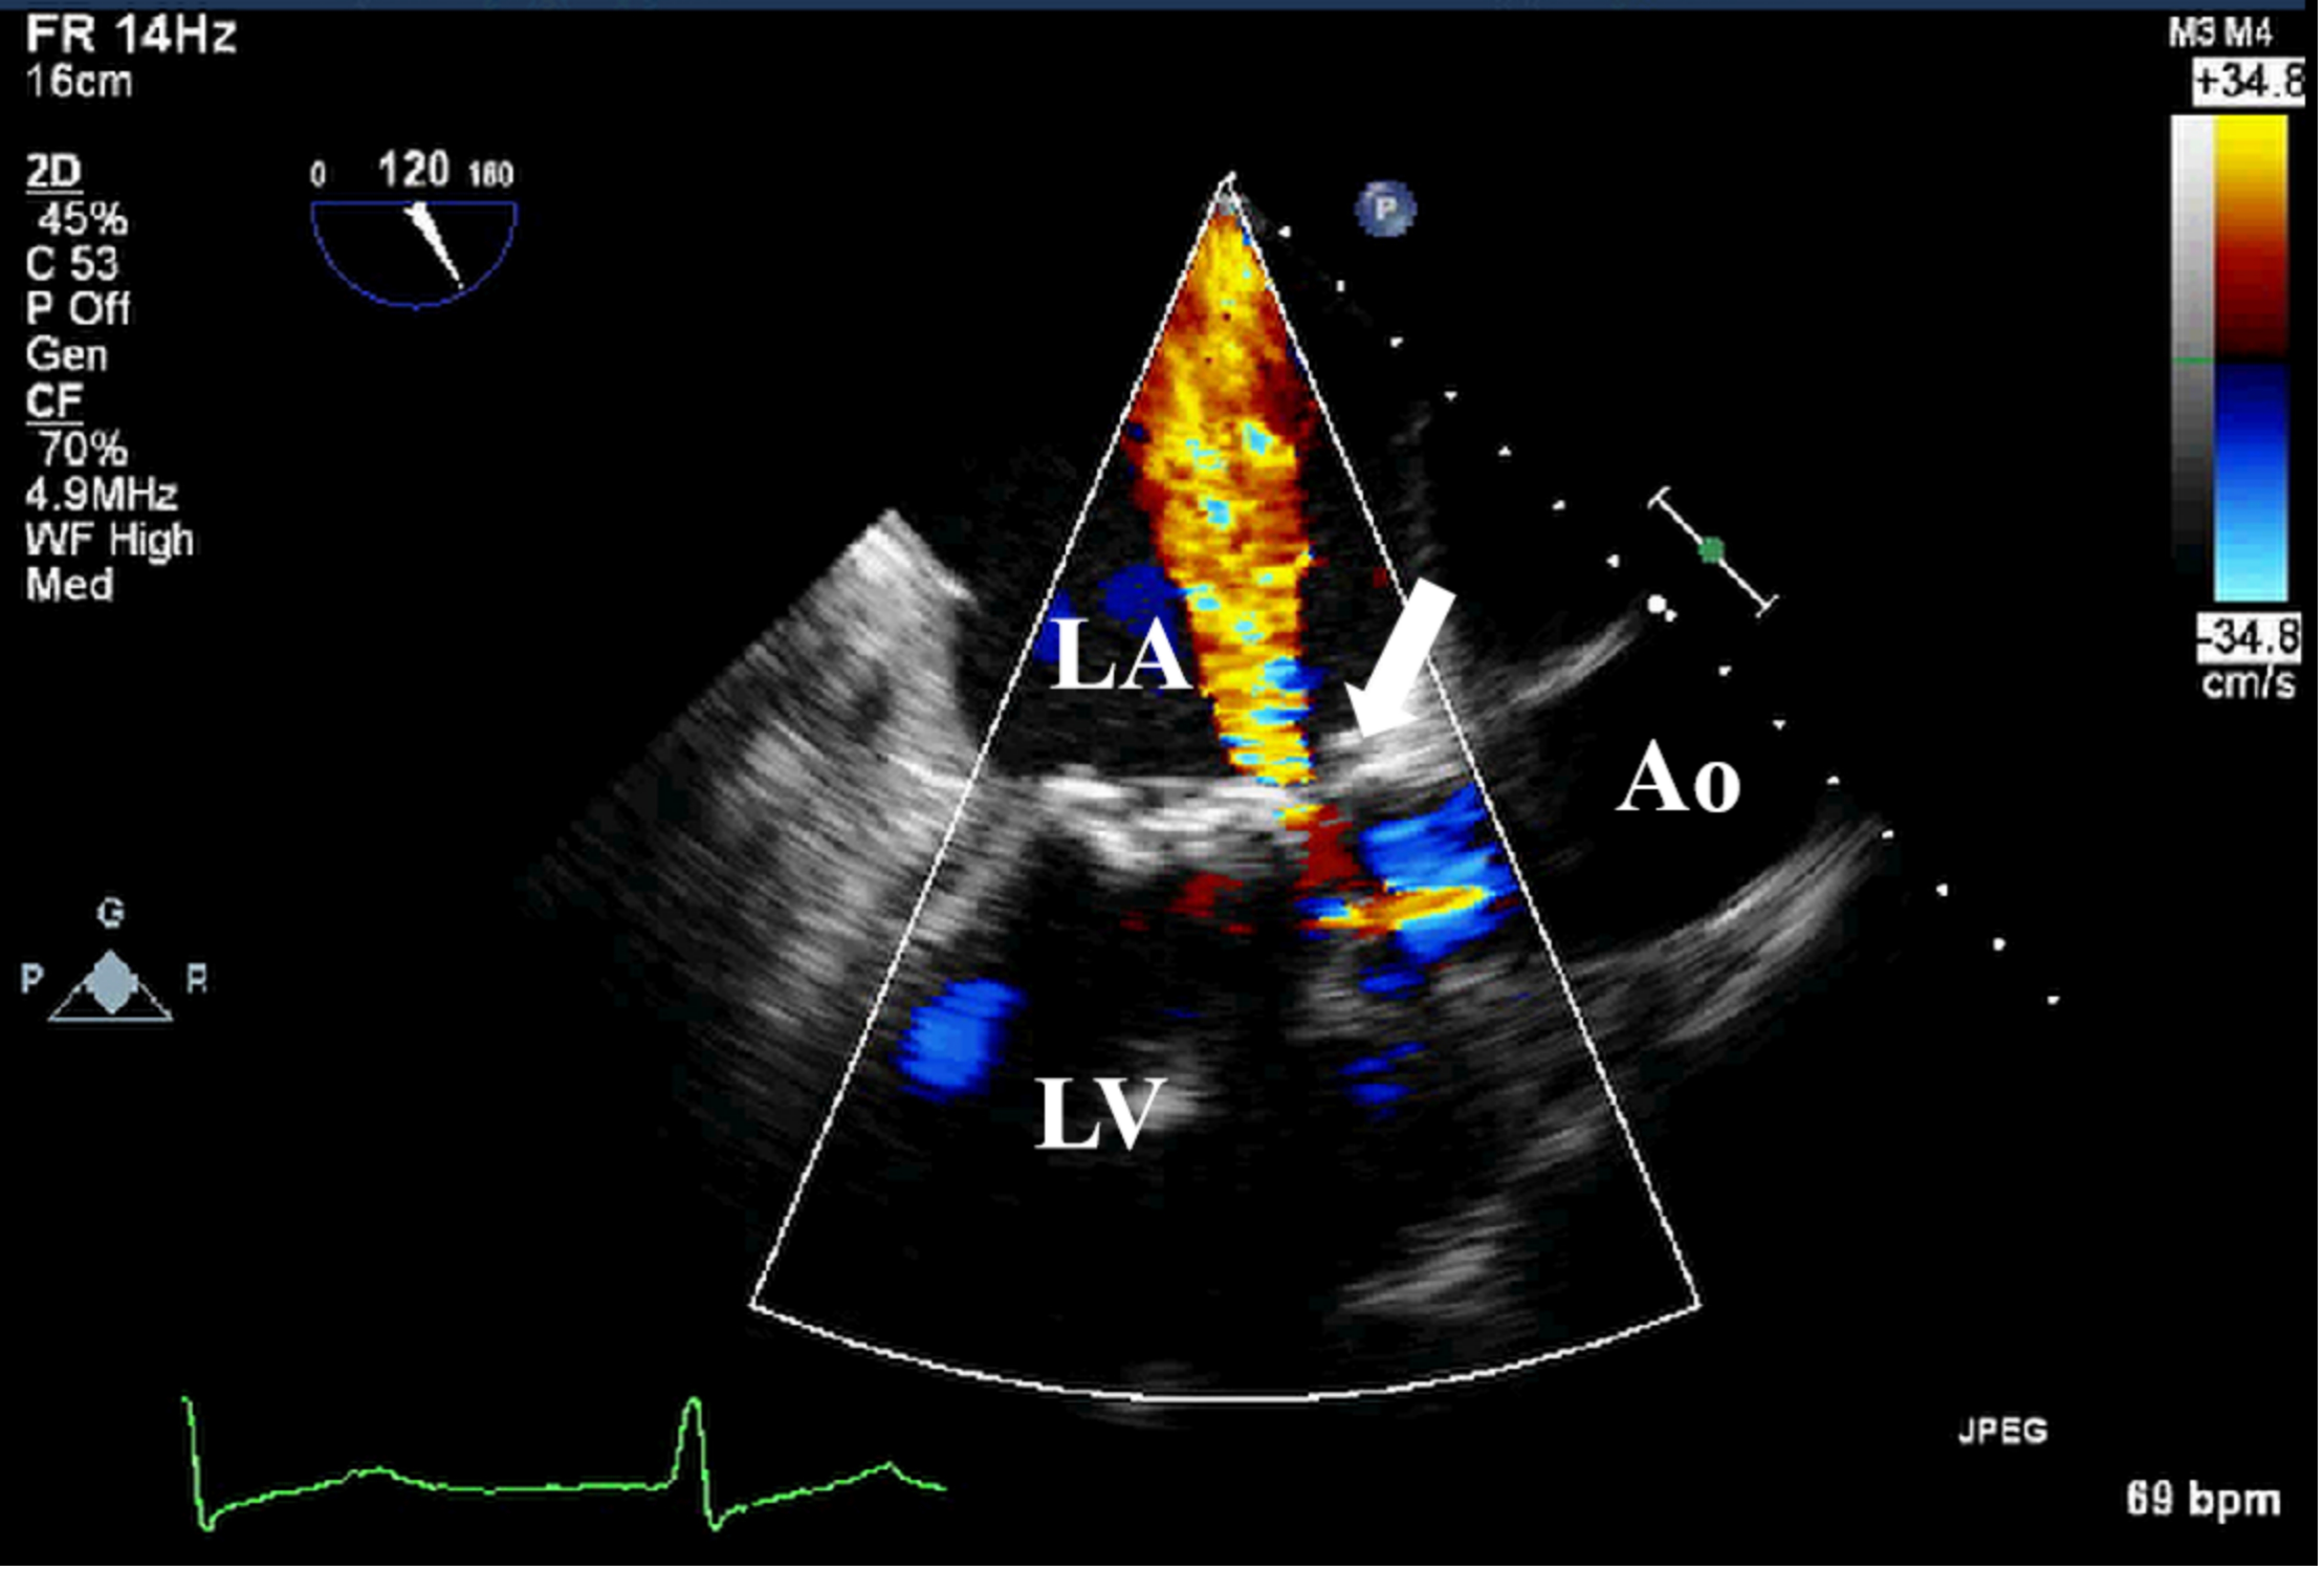

Echocardiography is the preferred imaging diagnostic modality for PVE, which can effectively identify valvular lesions and peri-valvular complications, such as abscesses, dehiscence, and paravalvular infections (Figs. 5,6,7). In the early postoperative period, attention should be paid to possible anatomical variations, such as edema-related changes, which may mimic pathological findings [23]. TEE is superior to TTE in terms of sensitivity (91% vs 65%), and its advantage mainly lies in being less susceptible to the interference of prosthetic valve artifacts. Among patients with suspected PVE, the NPV of TTE and TEE were both relatively high, ranging from 86% to 94% [9]. Furthermore, compared with two-dimensional (2D) TEE, 3D TEE can provide more comprehensive images of cardiac structures and has higher diagnostic value in the analysis of valvular lesions [46].

Fig. 6. TEE detection of bioprosthetic valve paravalvular leak. TEE shows paravalvular leakage (white arrow) of bioprosthetic mitral valve in mid-esophageal view. TEE, transesophageal echocardiography.